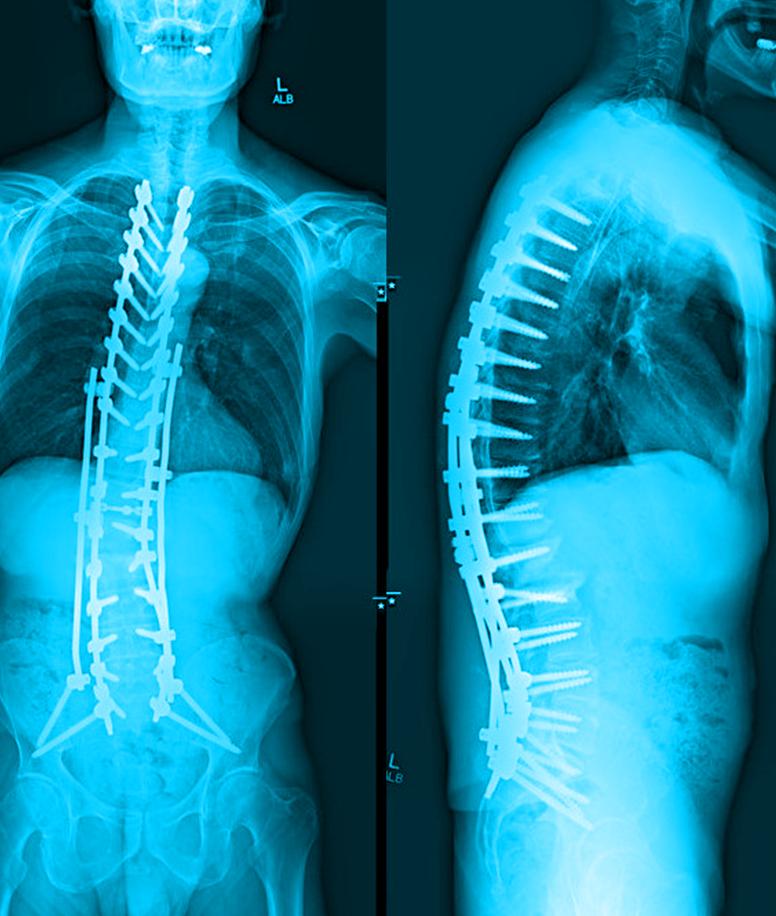

UT Southwestern’s Multidisciplinary Ataxia Clinic in the O’Donnell Brain Institute is a hub for research and care of patients with ataxia. This group of poorly understood, often disabling neurological disorders affects up to 150,000 people in the U.S., resulting in uncoordinated limb and trunk movements and falls, frequently leading to wheelchair confinement.

Led by Vikram Shakkottai, M.D., Ph.D., Associate Professor and Vice Chair for Basic Research in the Department of Neurology, as well as a member of the O’Donnell Brain Institute, the Multidisciplinary Ataxia Clinic is equipped to make important and needed strides in the diagnosis, study, and treatment of this difficult disease.

On the clinical side, patients in UT Southwestern’s Multidisciplinary Ataxia Clinic who are diagnosed with ataxia or a related disorder are provided sufficient information, in the right setting, to ensure they understand what the future holds for them and what approaches – both pharmacological and nonpharmacological – can resolve the etiology or symptoms of the disease.

Along with neurologists, the clinic also involves specialists in physical therapy, speech pathology, and occupational therapy to give patients broad-based care for the various aspects of their condition, which can include impairments of balance, speech, and hand dexterity. The clinic’s physical therapists can provide important input at the same time as clinical visits, a feature that is vital for patients with ataxia, who often travel long distances to receive expert treatment.

“Patients come from all over the country to receive care at the clinic,” Dr. Shakkottai says. “It’s incredibly humbling to know that we are one of the few ataxia programs – nationally or internationally – providing state-of-the-art clinical care.”